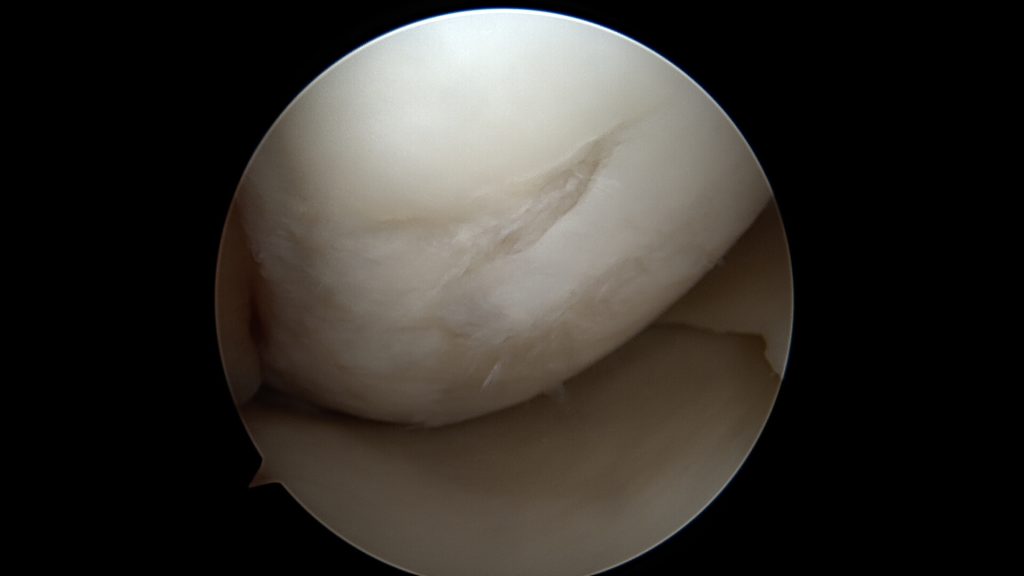

Do uszkodzenia chrząstki stawowej dochodzi w momencie urazu kolana, powtarzających się obciążeń czy chorób jak np. reumatoidalne zapalenie stawów. Może też być ona uszkadzana wtórnie poprzez inne elementy stawu (np.: uszkodzona łąkotka, ciało wolne). Wyróżniamy cztery stopnie jej uszkodzenia:

Uszkodzenia trzeciego i czwartego stopnia najczęściej wymagają leczenia operacyjnego. Same w sobie dają większe dolegliwości. Pozostawienie ich bez zaopatrzenia chirurgicznego może skończyć postępem oraz powiększaniem się uszkodzeń zarówno samej chrząstki jak i innych struktur w stawie. Leczenie zachowawcze w tych przypadkach nie przynosi oczekiwanych rezultatów.